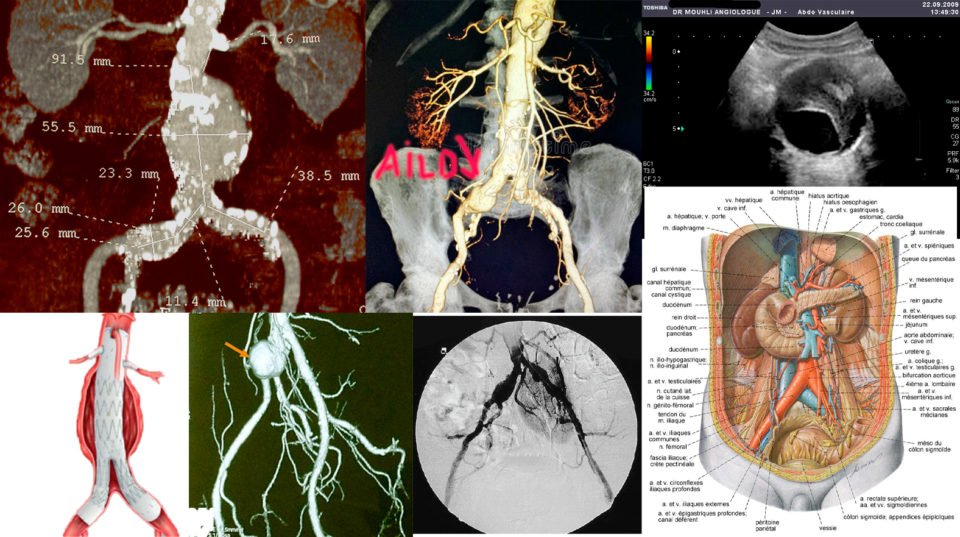

EXAMENS COMPLEMENTAIRES

Les examens les plus pertinents dans la prise en charge d’un anévrisme de l’aorte abdominale sont l’échographie Doppler artériel, l’angioscanner de l’aorte et des artères des membres inférieurs et l’angio-IRM.

L’échographie aorto-iliaque est le premier examen à demander pour confirmer le diagnostique. C’est un examen fiable, reproductible, non invasif et peu couteux. C’est l’examen utilisé en pratique courante pour la surveillance des petits anévrysmes et pour le dépistage. Il permet la recherche d’autres anévrysmes au niveau fémoro-poplités.

anevrisme-aorte-chirurgie-vasculaire-

L’angioscanner aorto-iliaque est plus invasif mais plus reproductible que l’échographie et moins opérateur dépendant. C’est l’examen de choix avant un traitement par endoprothèse ou par chirurgie classique. Il permet les mesures exactes (« sizing ») de l’anatomie de l’anévrysme, de l’aorte et des artères iliaques avant mise en place d’une endoprothèse. Il permet la recherche d’autres anévrysmes au niveau fémoro-poplités et d’étudier l’ensemble de l’aorte.